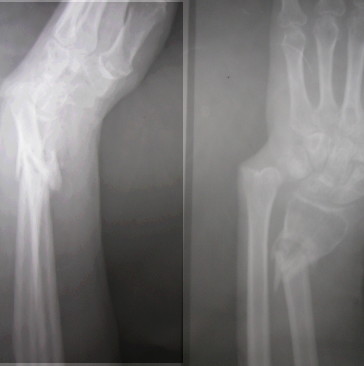

Dear All, Presenting this on behalf of a colleague of mine. 52 years old healthy male sustained a closed fracture of his distal forearm 3 mths ago.

Due to so many other injuries sustained by him, this has been inadequately treated and he has ended up today like this. Very prominent distal ulna and a mobile fracture distal radius. No infection. Wrist flexion, extension fully free and so also the fingers. He has a good grip too. He wants correction of this deformity. I have opined as follows. Exfix with two pins in the distal radius and two proximally. Distract gradually till the DRUJ is properly aligned. 1)If one is lucky some bone would have formed in between which may be good enough. Continue ExFix till it is solid. 2) If we find that no bone is forming by 2 weeks, we can distract a bit faster Once the DRUJ is aligned and there is gap left, we can put in a small piece of fibula under tension and continue the ExFix till it is consolidated. If one is used to, a plate can be used to fix the radius along with the graft. This will shorten the ExFix time Suggestions are welcome V M Iyer . Iyer Orthopaedic Centre, 103,Railway lines Solapur India